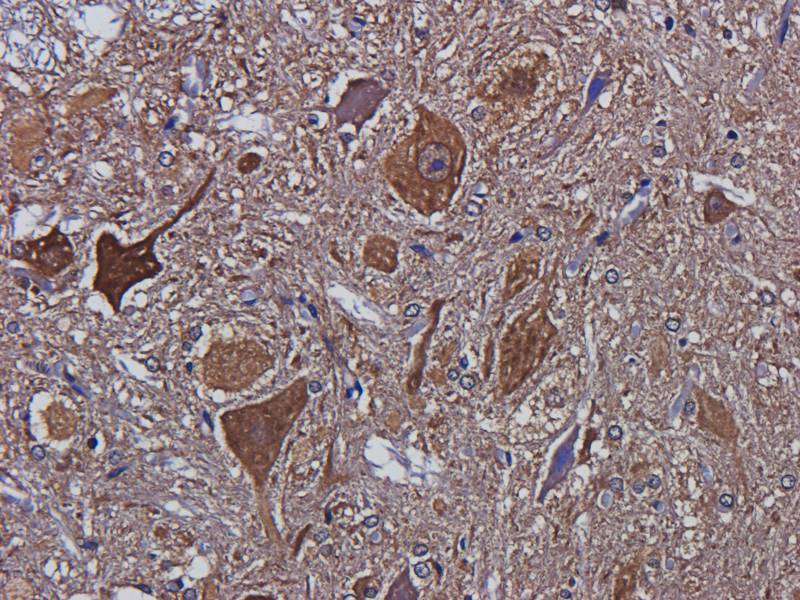

IHC staining of FFPE human brain with Ubiquitin antibody (clone PBQN-1). Required HIER: boil tissue sections in pH9 10mM Tris with 1mM EDTA for 10-20 min followed by cooling at RT for 20 min.